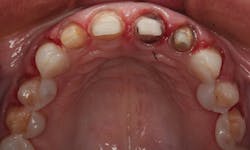

In the occlusal view in Figure 4, notice that her premolars are slightly rotated. Since both premolars were visible in her smile, it was decided to add porcelain veneers to the canines and premolars. The veneers would provide the appearance of well-aligned premolars, as well as add a lighter color. We both agreed that 10 restorations from second premolar to second premolar would be ideal.

Figure 4: Occlusal view of the patient’s initial smile